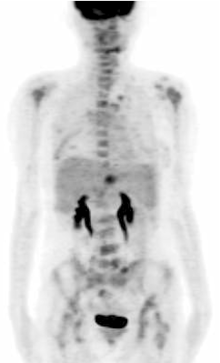

张国淳:该患者在完成了6个周期的XT方案之后又进行了一次PET疗效评价, 结果显示:与2009-08-25本院PET影像比较, 未见明确新发病灶, 原肝脏左叶病灶及乳腺病灶消失, 见图4。而CA15-3及CEA均降低至正常范围内。那么此时右乳局部复发灶是否应该进一步处理?